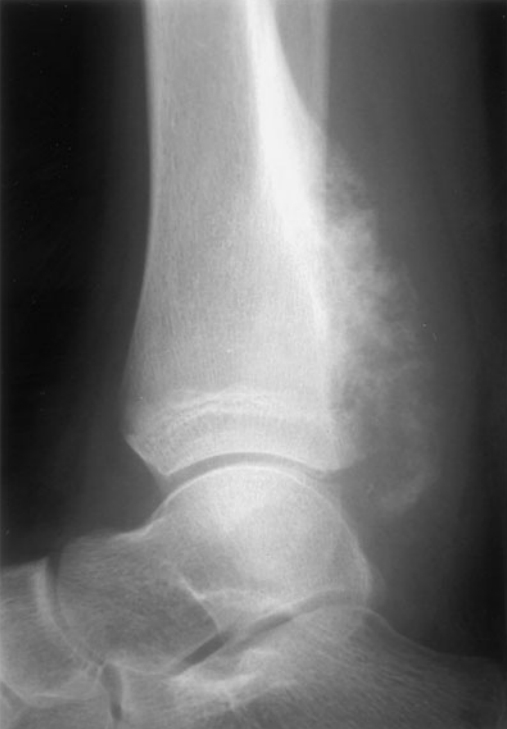

Slipped capital femoral epiphysis (SCFE)

demographics: typically occurs in overweight adolescents or thin pt who had underwent rapid growth spurt

symptoms: presents with a limp. Pain when moving hips

labs: Radiographically, the capital femoral epiphysis is separated from the neck of the femur and remains in the acetabulum as the rest of the femur moves anteriorly.,